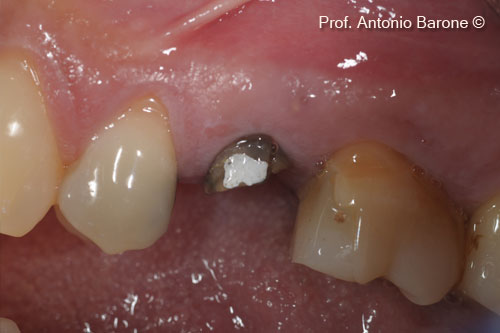

Hình ảnh lâm sàn mặt nhai sau khi bộc lộ implant

Trụ cấy ghép